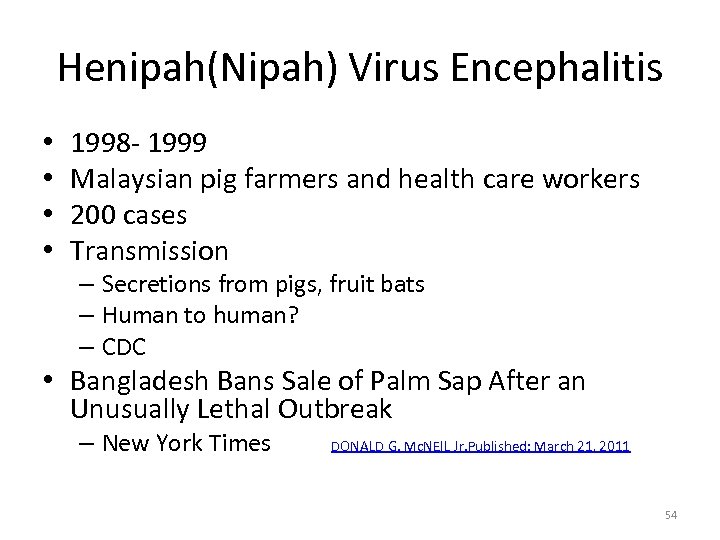

Henipah(Nipah) Virus Encephalitis • • 1998 - 1999 Malaysian pig farmers and health care workers 200 cases Transmission – Secretions from pigs, fruit bats – Human to human? – CDC • Bangladesh Bans Sale of Palm Sap After an Unusually Lethal Outbreak – New York Times DONALD G. Mc. NEIL Jr. Published: March 21, 2011 54